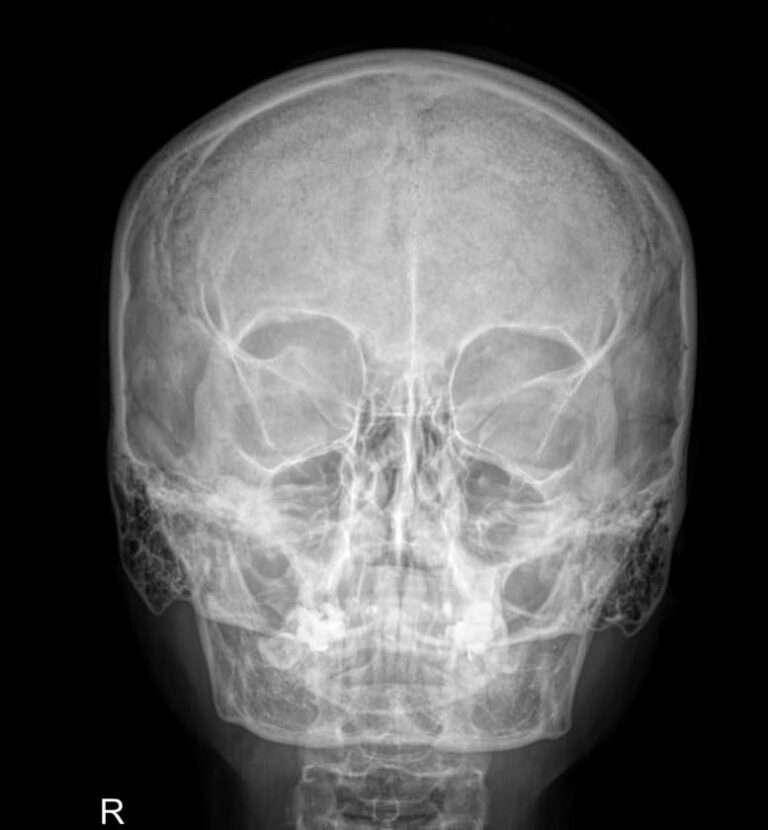

Череп устроен крайне сложно, так как содержит в себе множество важнейших органов: головной мозг и его кору, черепно-мозговые нервы, железы внутренней секреции, органы зрения, слуха и частично ― дыхательной и пищеварительной систем. Для каждого есть свой специфический участок с уникальным строением. Несмотря на то, что большинство этих органов относительно мягкие, они оказывают свое влияние на твердые кости черепа, оставляя на них следы при патологических изменениях. Поэтому рентген, как наиболее доступный и эффективный метод диагностики костной ткани, назначается одним из первых.

Снимки черепа требуют специального подхода во время рентгенодиагностики. Одно из основных требований ― соблюдение симметричности правой и левой стороны при фронтальной, то есть прямой рентгенографии. Также часто назначают снимок в боковой проекции, реже ― подбородочную, затылочную и прицельные снимки определенных костей.